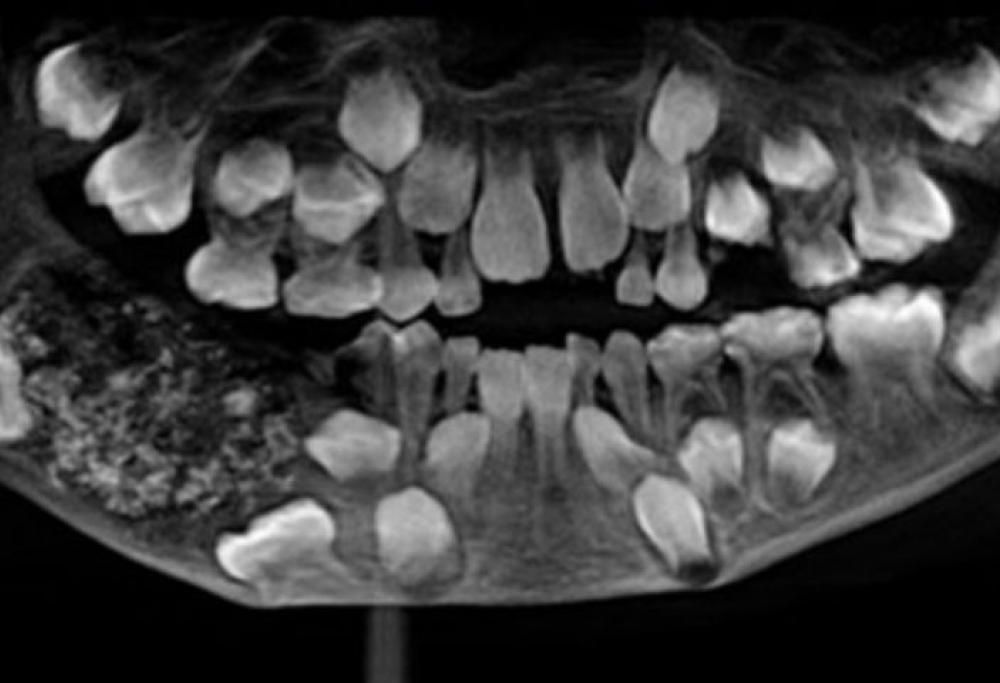

Il caso clinico decisamente anomalo è stato trattato a Chennai, in India. Un bimbo di 7 anni è stato portato al Saveetha Dental College perché aveva la mascella molto gonfia.

Quando i medici hanno sottoposto il bambino ai primi accertamenti hanno scoperto con enorme sorpresa di cosa si trattava: tecnicamente viene definito un odontoma composto, probabilmente dovuto a un sovrannumero di germi dentari.

In una sacca della mascella inferiore del bambino erano annidati 526 piccolissimi denti, dalle dimensioni variabili tra 0,1 e 15 millimetri. Ognuno di questi denti era composto di corona, radice e smalto.

I dentisti hanno dichiarato: “Questo è il primo caso in assoluto documentato in tutto il mondo in cui sono stati trovati così tanti piccoli denti in un singolo individuo”. Per estrarre tutti i denti hanno impiegato circa 5 ore.